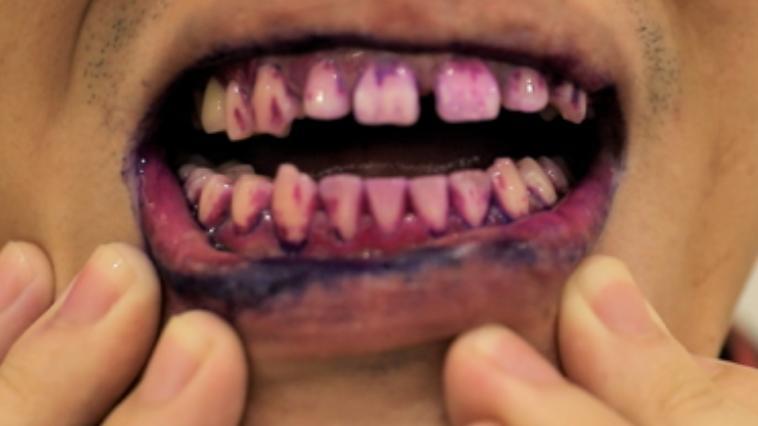

丁香醫生做過一個牙菌斑顯色劑實驗,結果發現,即使刷過牙,仍有牙菌斑殘留。

刷完牙 vs 24 小時後

均使用牙菌斑顯色劑

顏色越紅,表示牙菌斑越多

圖片來源:丁香一位實驗小哥

這離不開幾個常見刷牙問題 :沒刷到位,刷牙時間、角度都不對;牙縫沒清潔,我們不易刷到牙縫、牙內側、牙齒與牙齦的交界處;漏刷的地方,時間一長,殘留在嘴巴里的牙菌斑,就能大量積累。

如果放任不管,就可能菌斑堆積 → 齦炎/牙周炎 → 牙齦+下方牙槽骨被破壞 → 牙齦高度隨着降低→ 牙根外露,牙齒間出現「黑三角」 → 看上去牙縫變大。